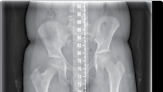

| Operative planning | |||

| Recent radiographs must be available. These should include full leg length views, in the anteroposterior plane, of both lower limbs with the patellae facing forwards and appropriate lateral views. The mechanical and anatomical axes need to be assessed on both legs. If both legs are ‘abnormal’, standard angles are used for calculations. | |||

| Leg length discrepancy | |||

| Assessment is made from history, examination and radiological findings. Care must be taken to differentiate true from apparent causes of leg length discrepancy. | |||